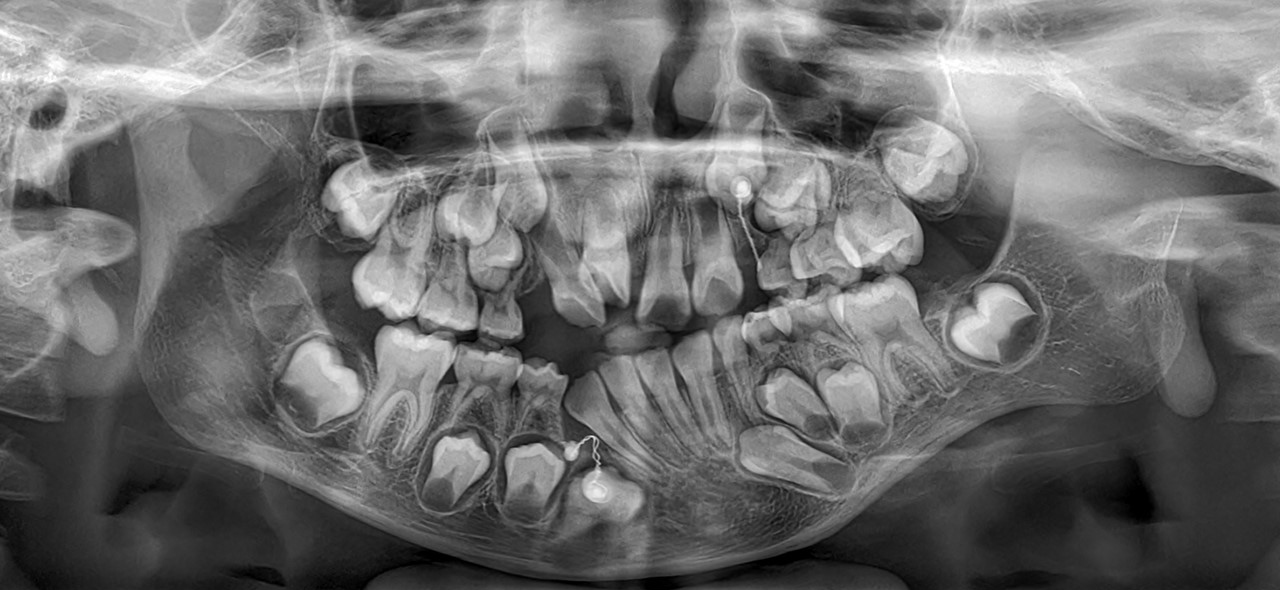

Caso Clinico N° 749 EVALUACIÓN DE ODONTOMA COMPUESTO

4 Dic 2025